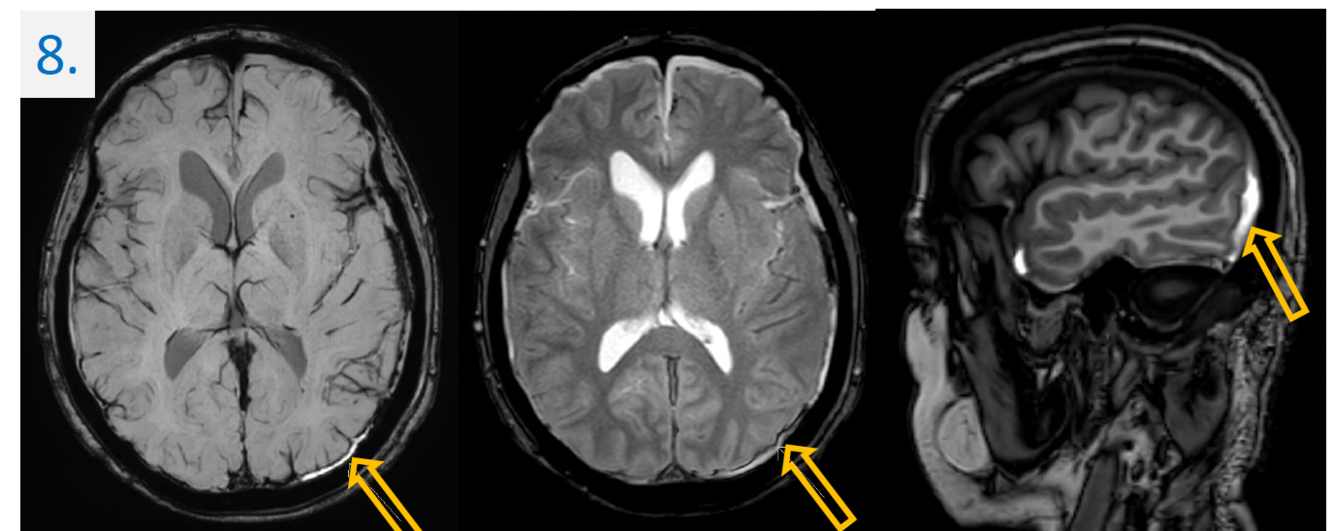

8.